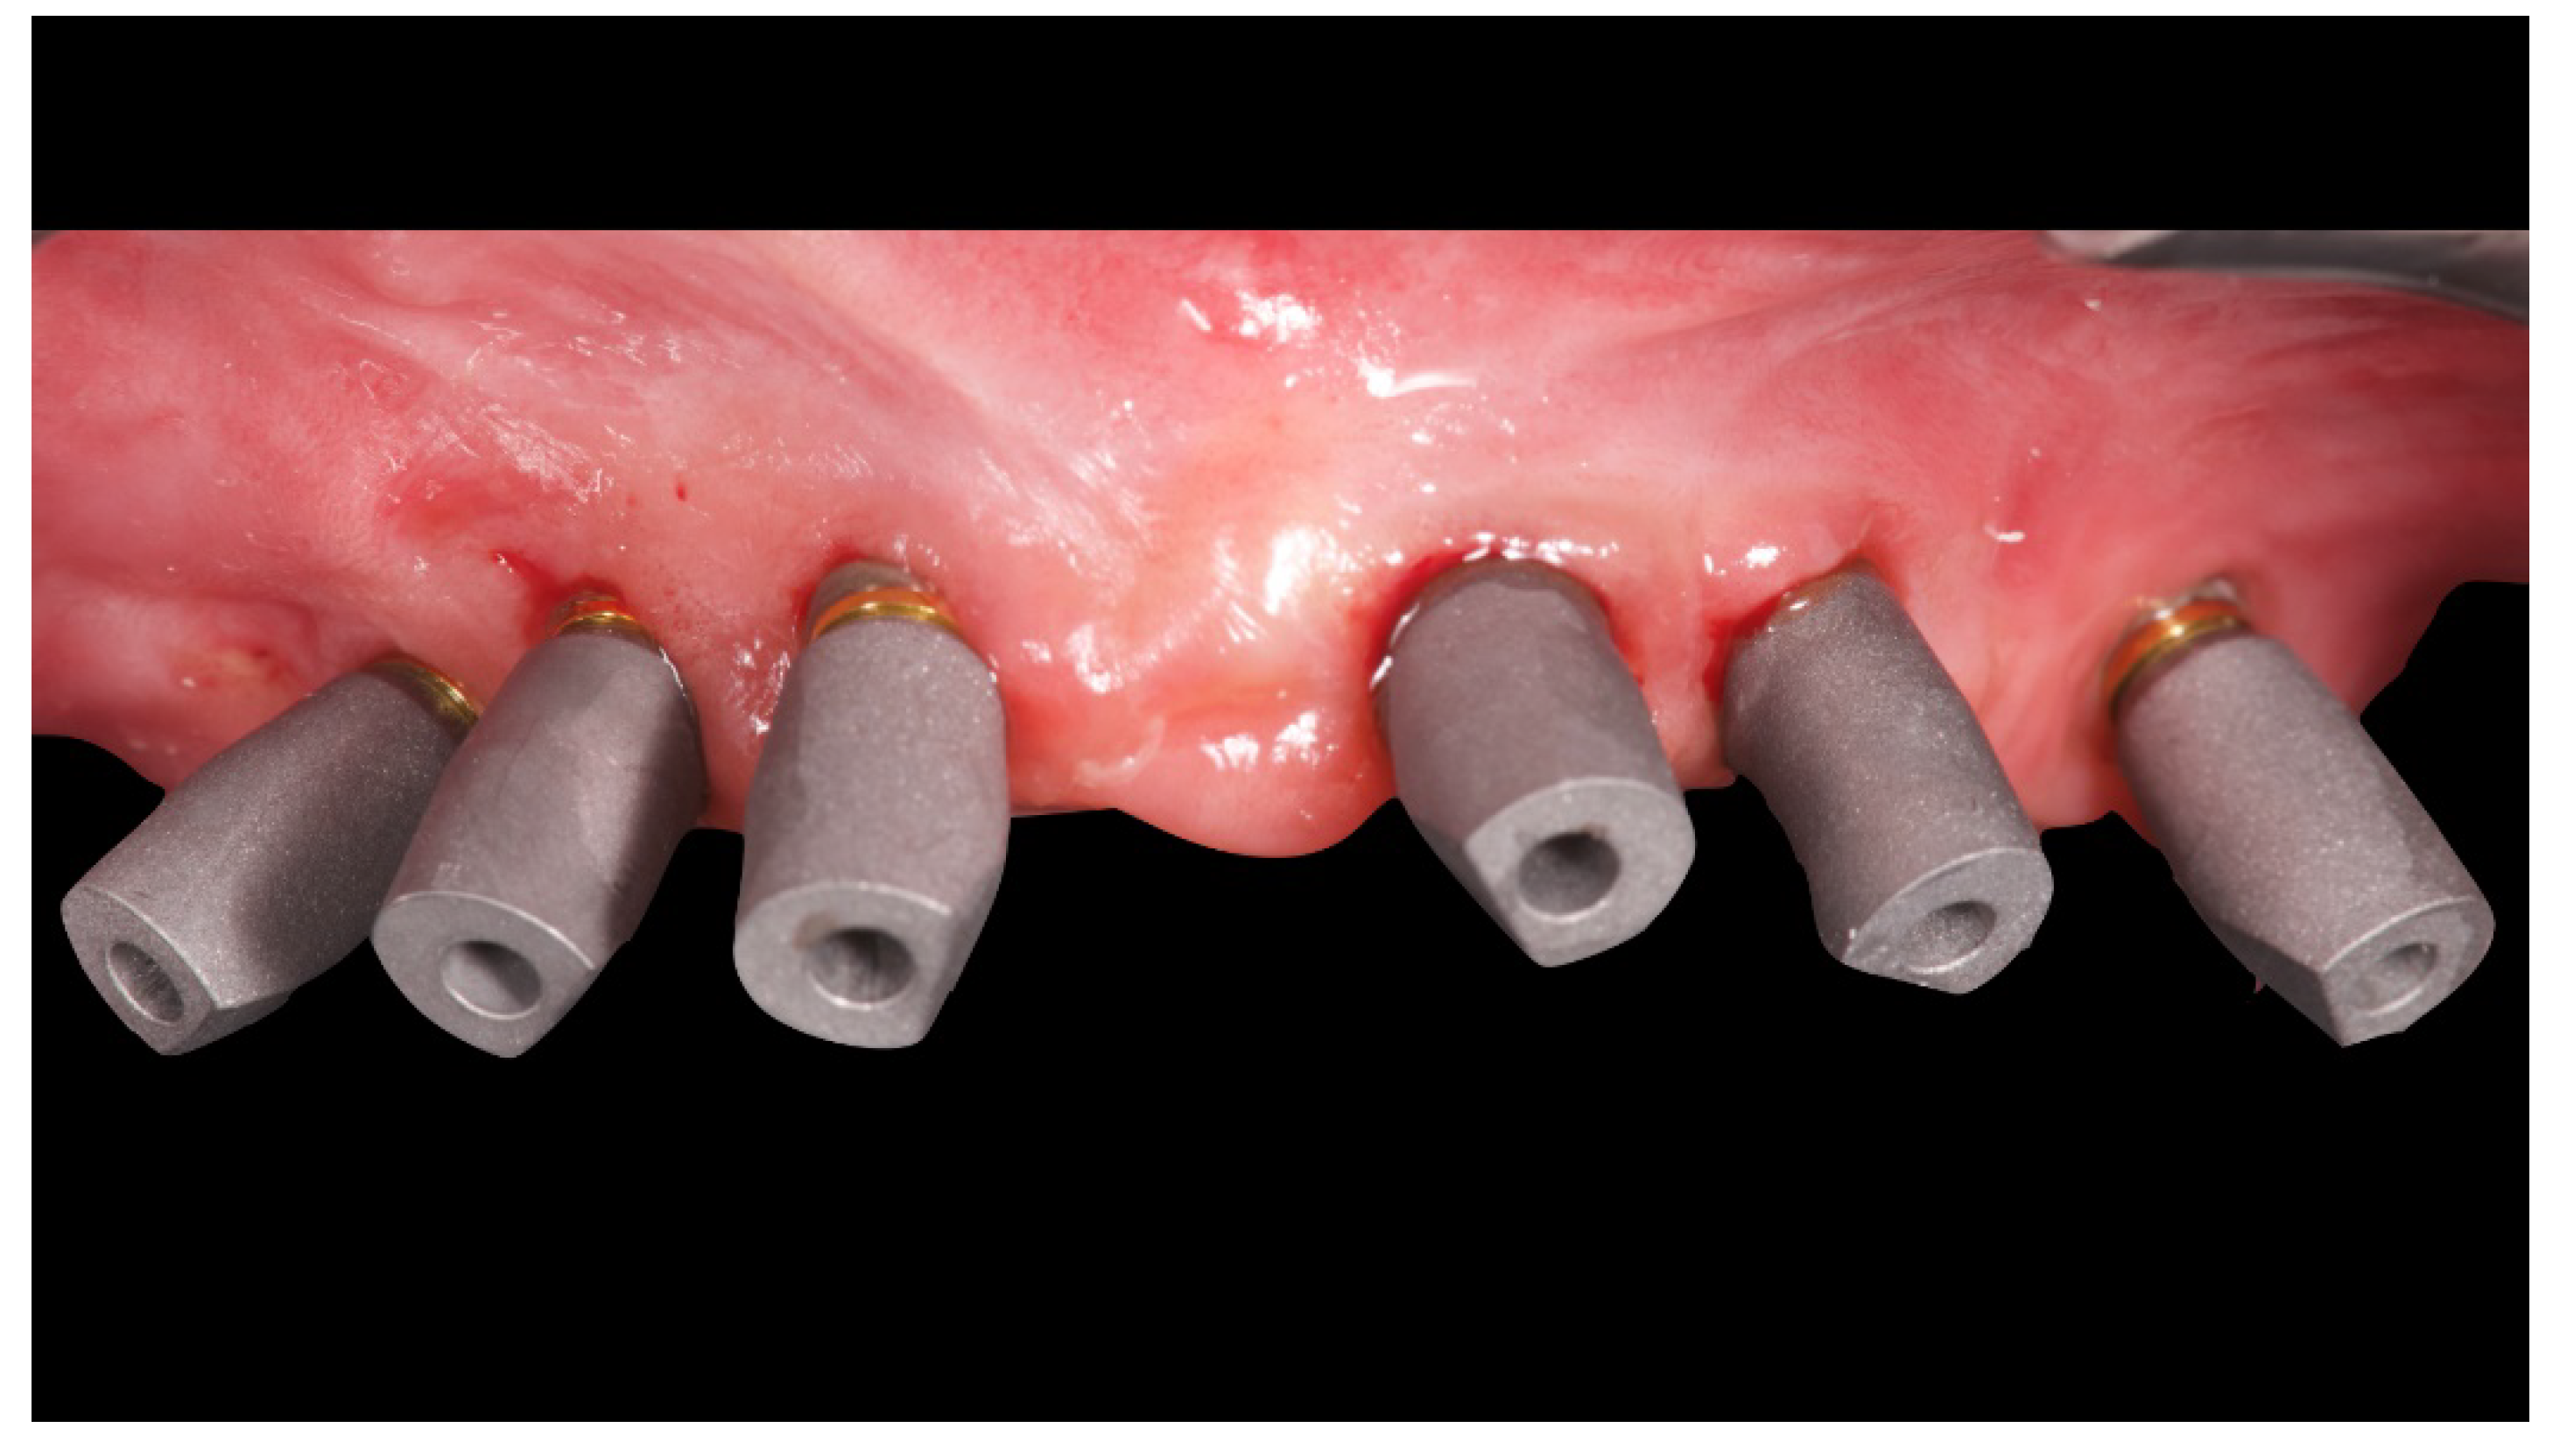

Figure 7.

Scan bodies mounted on OT Equator. Note the strong disparallelism among the dental implants.